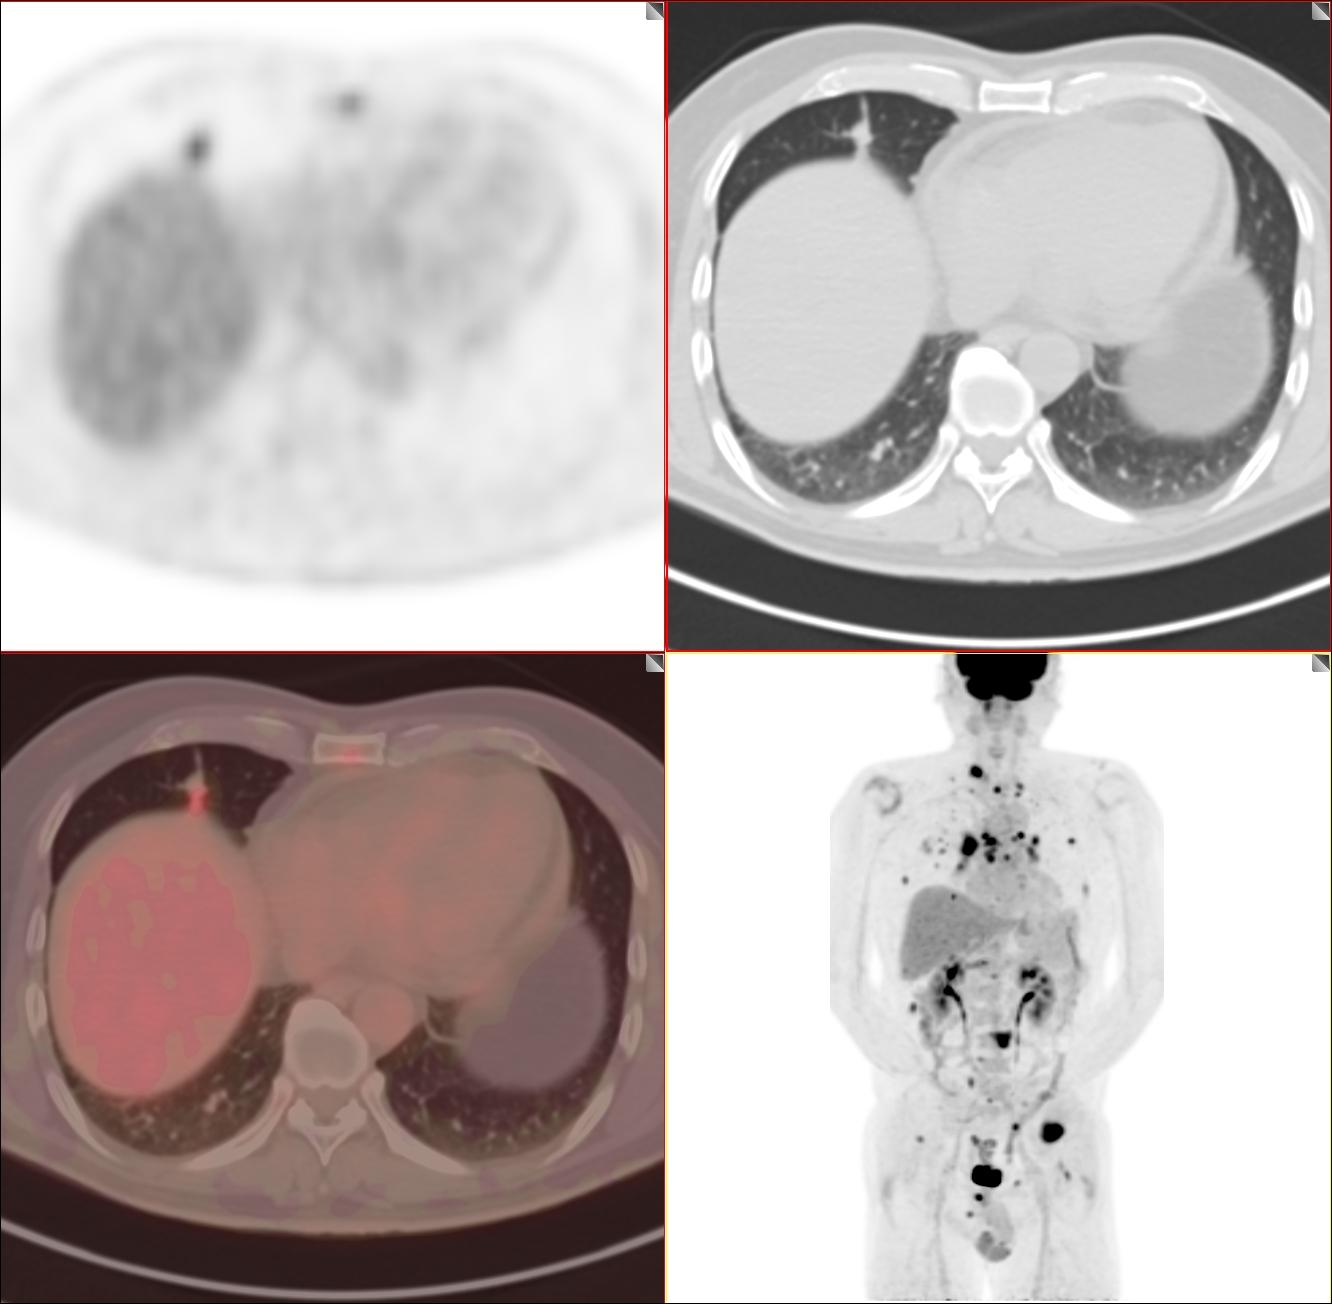

原因是这么一回事,遇到1例肺结节患者,病灶最大直径约1.5cm结节,结果转移得一塌糊涂!双肺弥漫性转移(肺内多达几百个病灶)、全身多发骨转移、全身多发淋巴结转移。

就是这么一个小病灶。为了不引起大家不适,我不发更多的图片

患者仅有50多岁,巫医生的心就落到了谷底。追寻病史,患者间隔1年没有体检,就成了现在的这个状况,肺癌四期。趋势这个实性的病灶有点大,如果再1cm以内做一个检查,相信不会发生这么严重的转移。